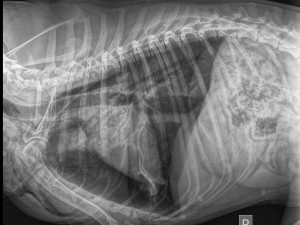

Čtyřmi kulkami trefil fenku Maggie policista, který zasahoval v Praze 10. Podle organizace Nebelvíra, která se případem zabývá, jen štěkala ve tmě a policista bezdůvodně vystřelil. Policie ale naopak tvrdí, že použil služební zbraň, protože na něj pes útočil. Vše ale prověří kontrola.

Jedna kulka zasáhla hrudník, svezla se po hrudní kosti a nezasáhla tak orgány. Další tři pak packu, kterou zřejmě budou muset amputovat.